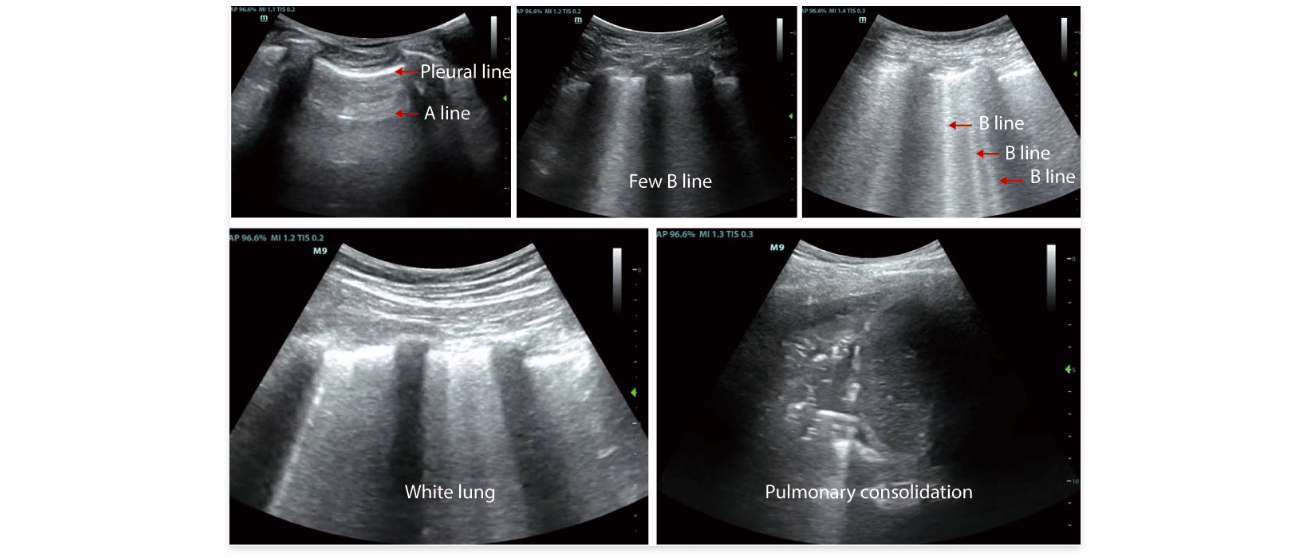

• 1. Professional lung examination mode to observe changes in lung conditions